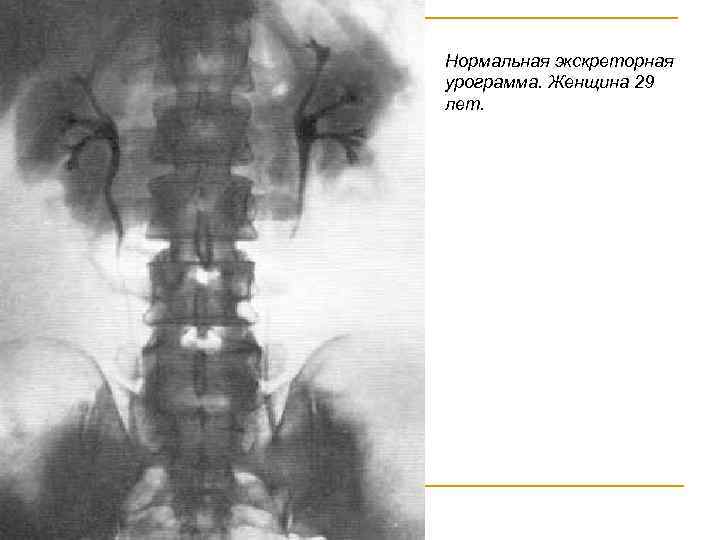

Нормальная экскреторная урограмма. Женщина 29 лет.